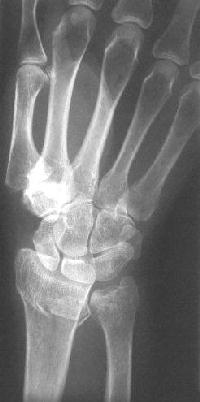

Clinical Example: Distraction plate fixation distal radius fracture

distal radius fracture